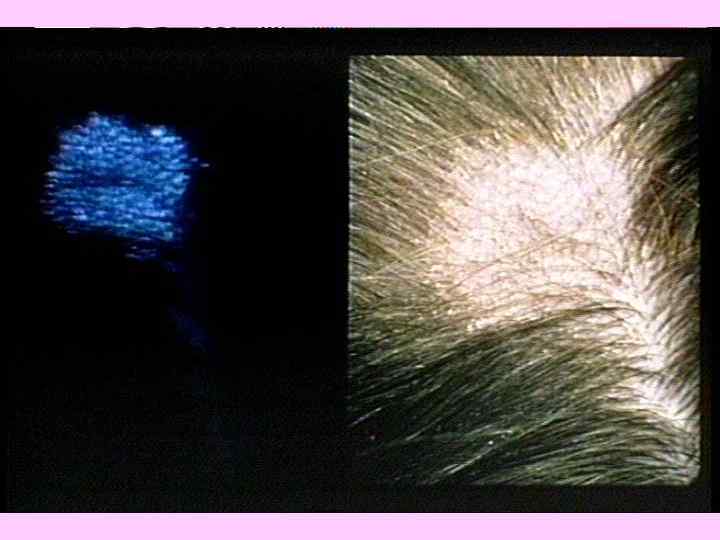

КЛАССИФИКАЦИЯ ГРИБКОВЫХ ЗАБОЛЕВАНИЙ ПОВЕРХНОСТНЫЕ МИКОЗЫ ТРИХОФИТИЯ МИКРОСПОРИЯ ЭПИДЕРМОФИТИЯ КАНДИДАМИКОЗ Дерматофитозы (около 40 видов возбудителей) ГЛУБОКИЕ И СИСТЕМНЫЕ МИКОЗЫ КАНДИДАМИКОЗ ГИСТОПЛАЗМОЗ КРИПТОКОККОЗ КОКЦИДОИДОЗ АСПЕРГИЛЛЕЗ БЛАСТОМИКОЗ

ДЕРМАТОФИТЫ «АНТРОПОФИЛЬНЫЕ» Microsporum audounii Trichophyton rubrum Trichophyton schoenlenii «ЗООФИЛЬНЫЕ» Microsporum canis «ГЕОФИЛЬНЫЕ» Microsporum gypseum (трихифития)